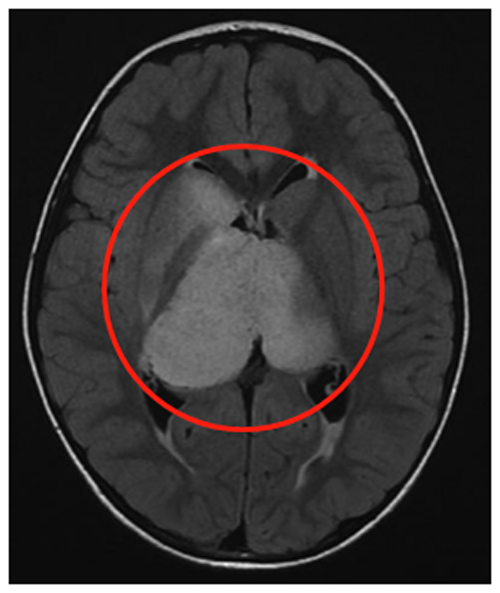

患者是一名6歲男童,癥狀為頭痛、間歇性左上肢震顫。MRI(FLAIR序列)顯示一個兩側(cè)丘腦腫瘤,右比左大,尾狀核的右頭部也參與其中。腦室輕度增大,膈膜水腫,腫瘤內(nèi)部囊腫。因此,Rutka教授為其先行左額部內(nèi)窺鏡活檢和鼻中隔造瘺術(shù),再行左枕腦室-腹腔分流術(shù)。

組織病理診斷為WHO III級間變性星形細胞瘤,H3K27M、p53、BRAF V600E突變免疫陰性。MIB-1增殖指數(shù)為40%。至此,Rutka教授為患兒制定了周密的綜合治療方案,患兒開始同時接受替莫唑胺(TMZ)和放射治療(59.4 Gy),并接受累計劑量為200 mg/m2的12個周期的持續(xù)替莫唑胺治療。該男孩在確診后15個月放射學表現(xiàn)穩(wěn)定,癥狀也得以緩解,生活質(zhì)量有所提升。